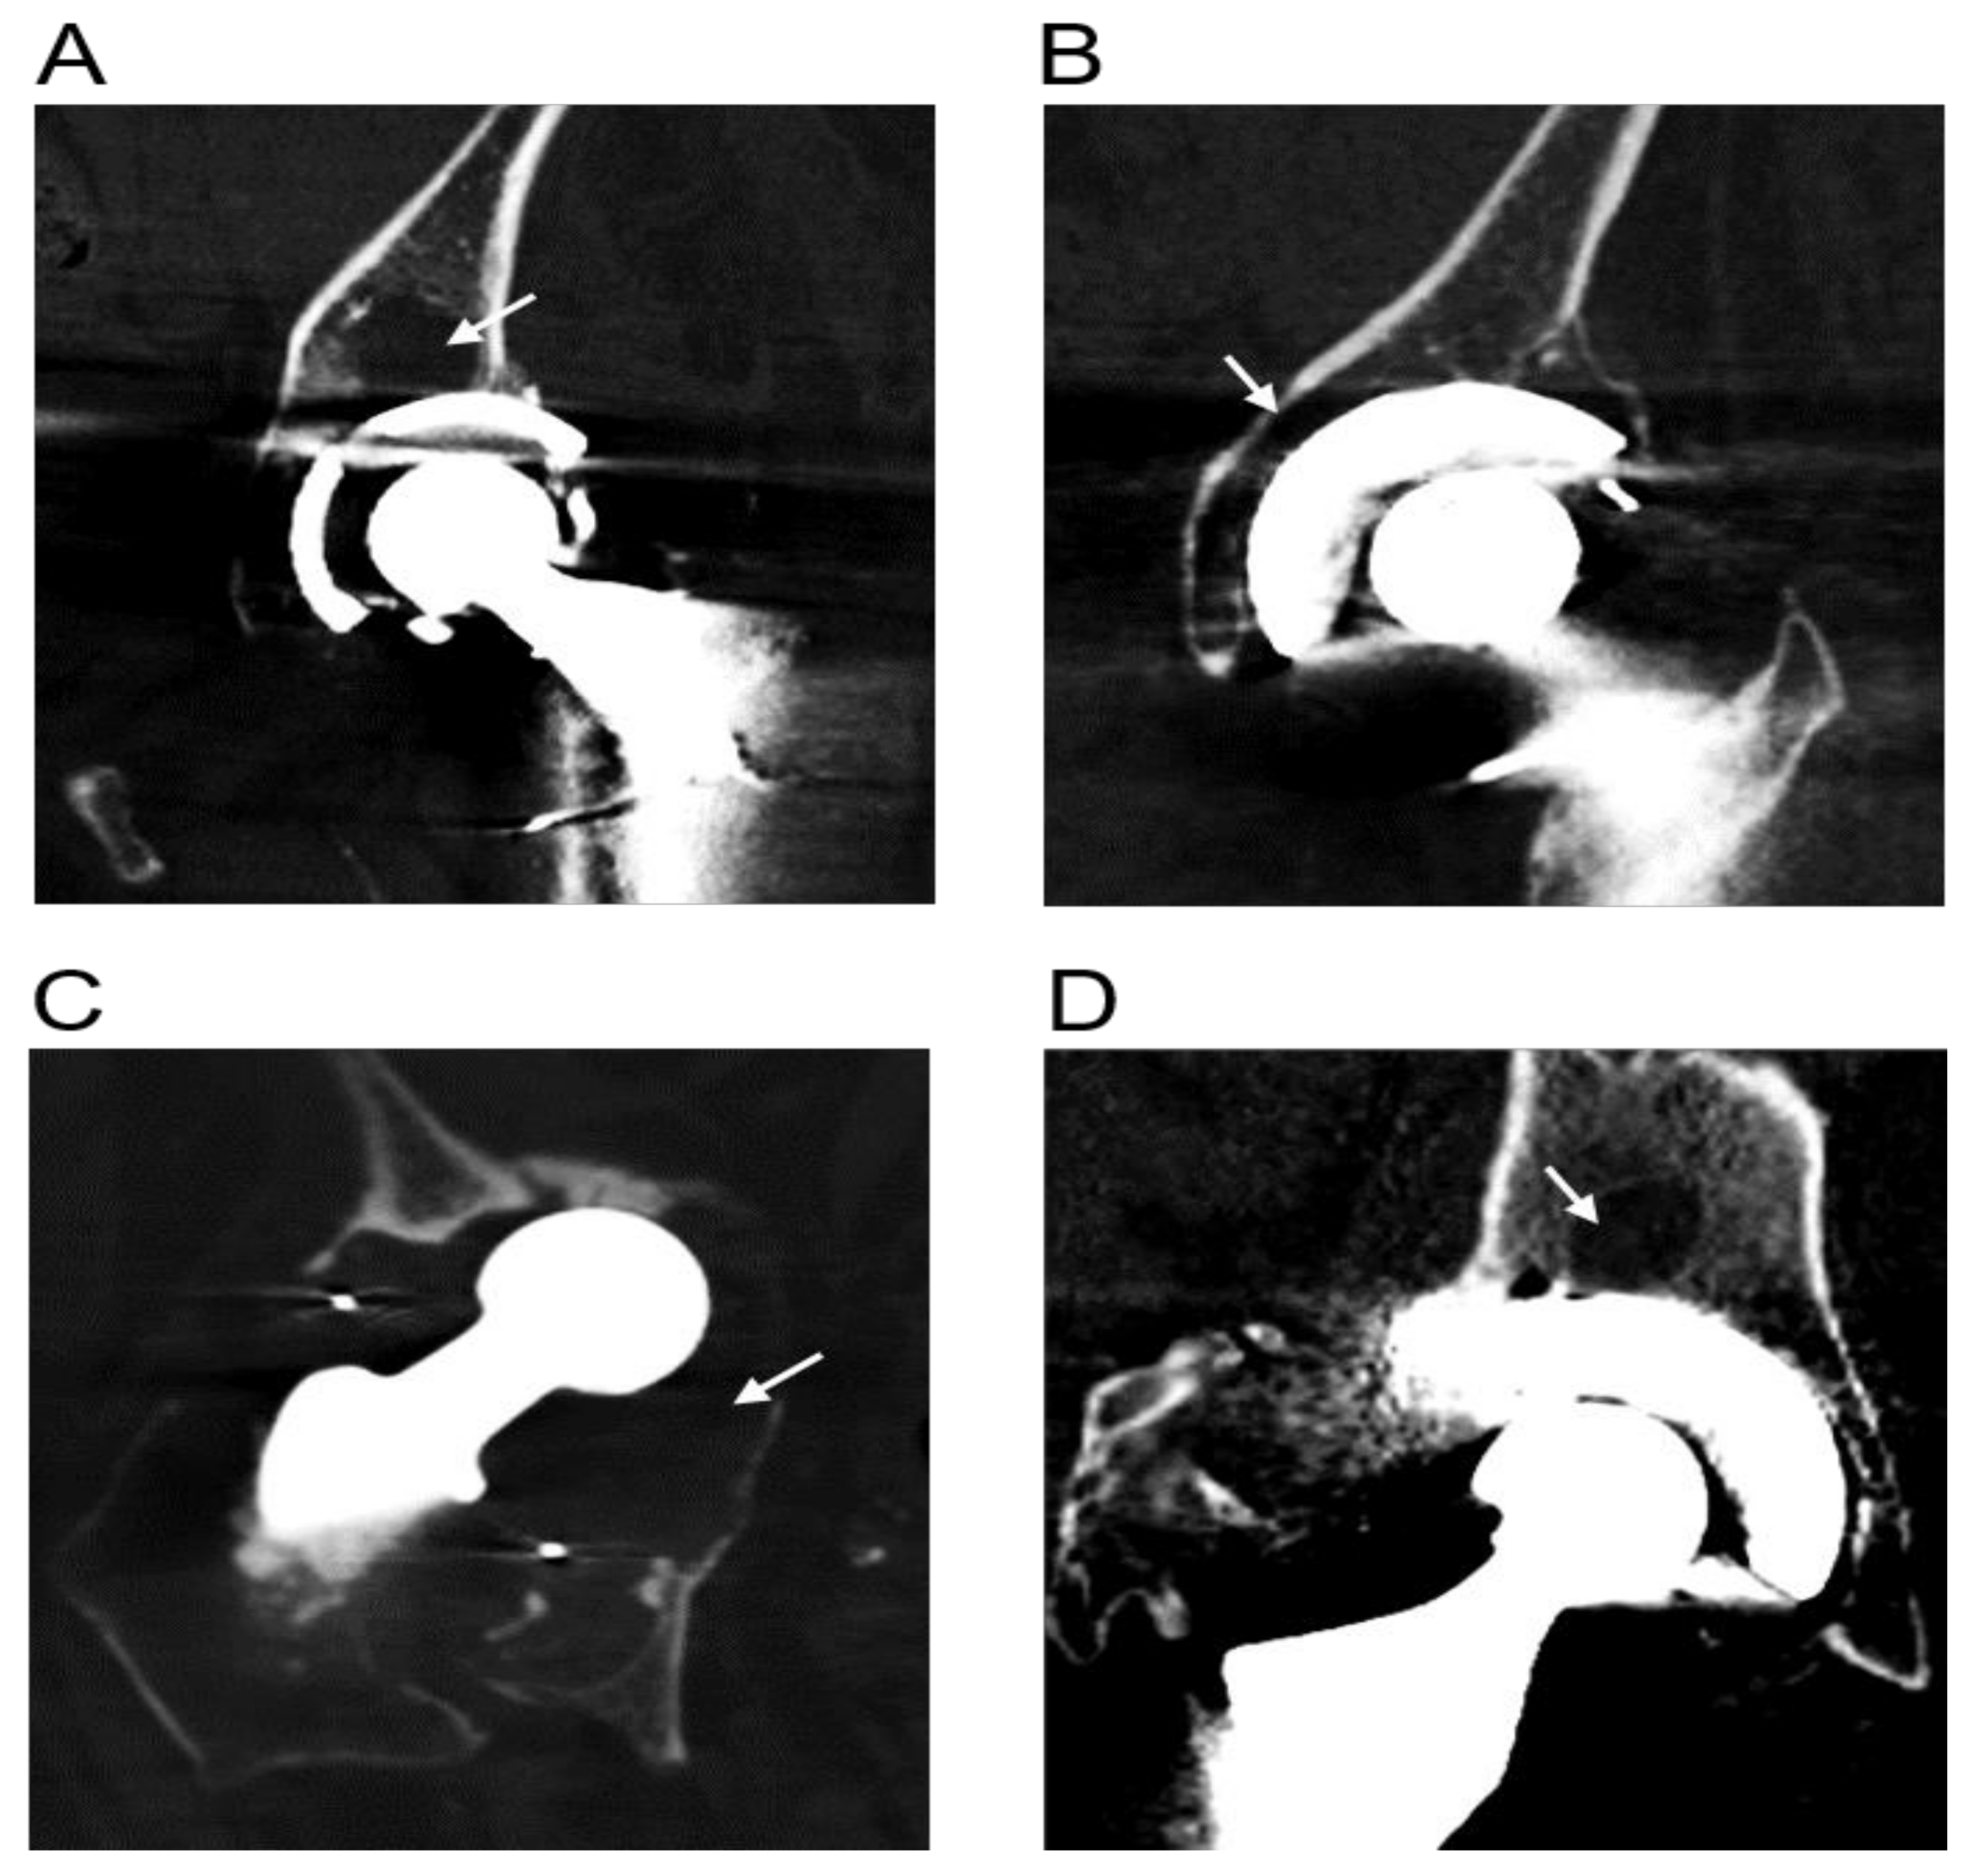

3.1. Radiographic Evidence of Osteolysis in Patients Undergoing Revision THR